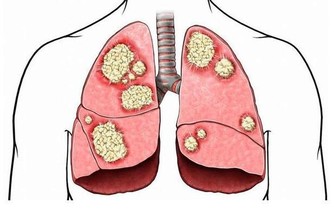

兒童期超重、肥胖會增加高血壓、糖尿病、高甘油三酯、代謝綜合徵等的發生風險,

肥胖還會影響兒童青春期發育,危害呼吸系統及骨骼,甚至對心理、行為、認知及智力產生不良影響。